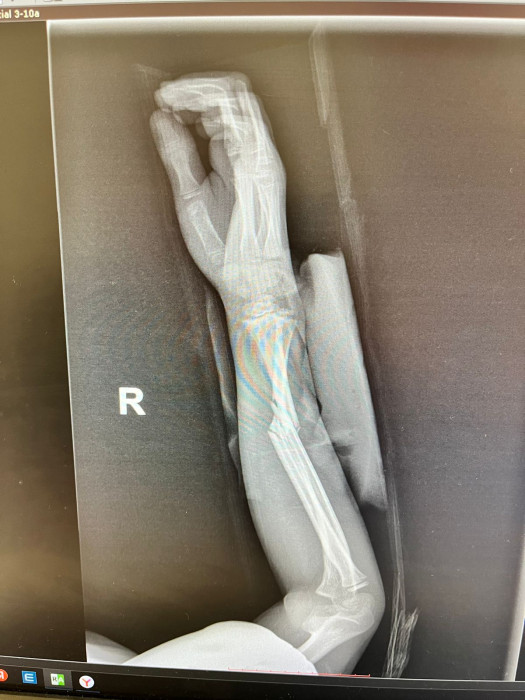

Кораблёв С.Г.: Да, вот ребёнок, 8 лет. Видно, перелом двух костей предплечья.

Кораблёв С.Г.: Адам, ещё раз: это второй снимок — боковая проекция. Это он на гипсе, это первичная репозиция, соответственно. И, вот, буквально они сделали на днях снимки, и всё прекрасно. Доктора сами удивились.

Кораблёв С.Г.: Две недели. Вот вы мне тогда дали рекомендации.

Кораблёв С.Г.: К физиотерапии, да. Я дополнительно делал немного мануального вытяжения, физиотерапию, ударно-волновую терапию, электромагнитную стимуляцию. Также работал по 10 минут 4 дня с поющей чашей HEALINGBOWL. И через день я брал чашу ноты До.

Суриков В.П.: Какой частоты чаши была? Низкочастотная, тональности До?

Кораблёв С.Г.: Да, да.

Суриков В.П.: То есть у нее была частота около 130 Гц. И в итоге, вывод какой сделаем?

Кораблёв С.Г.: Я забыл сказать, что немного неправильно выбрали тип операции. Соответственно, здесь они поставили спицы, видите, но полностью сопостава не было. И там была еще ошибка, видимо, студенты удаляли, и после этого резко дёрнули, и перелом съехал в это положение. Это после операции. Они сказали: «Давайте подождем». И вот их выписали. Я смог забрать пациента себе, и вел на реабилитацию, поменял гипс, стянул, и мы каждый день работали-работали. И потом я с вашим методом познакомился.

Суриков В.П.: Настолько ровно получилось.

Кораблёв С.Г.: Ну вот факт, такой есть факт. То есть здесь не просто перелом, то есть еще спицы сделали, он ходил с ними, сняли, съехало, и угловая деформация еще больше стала. И сейчас уже такой результат.